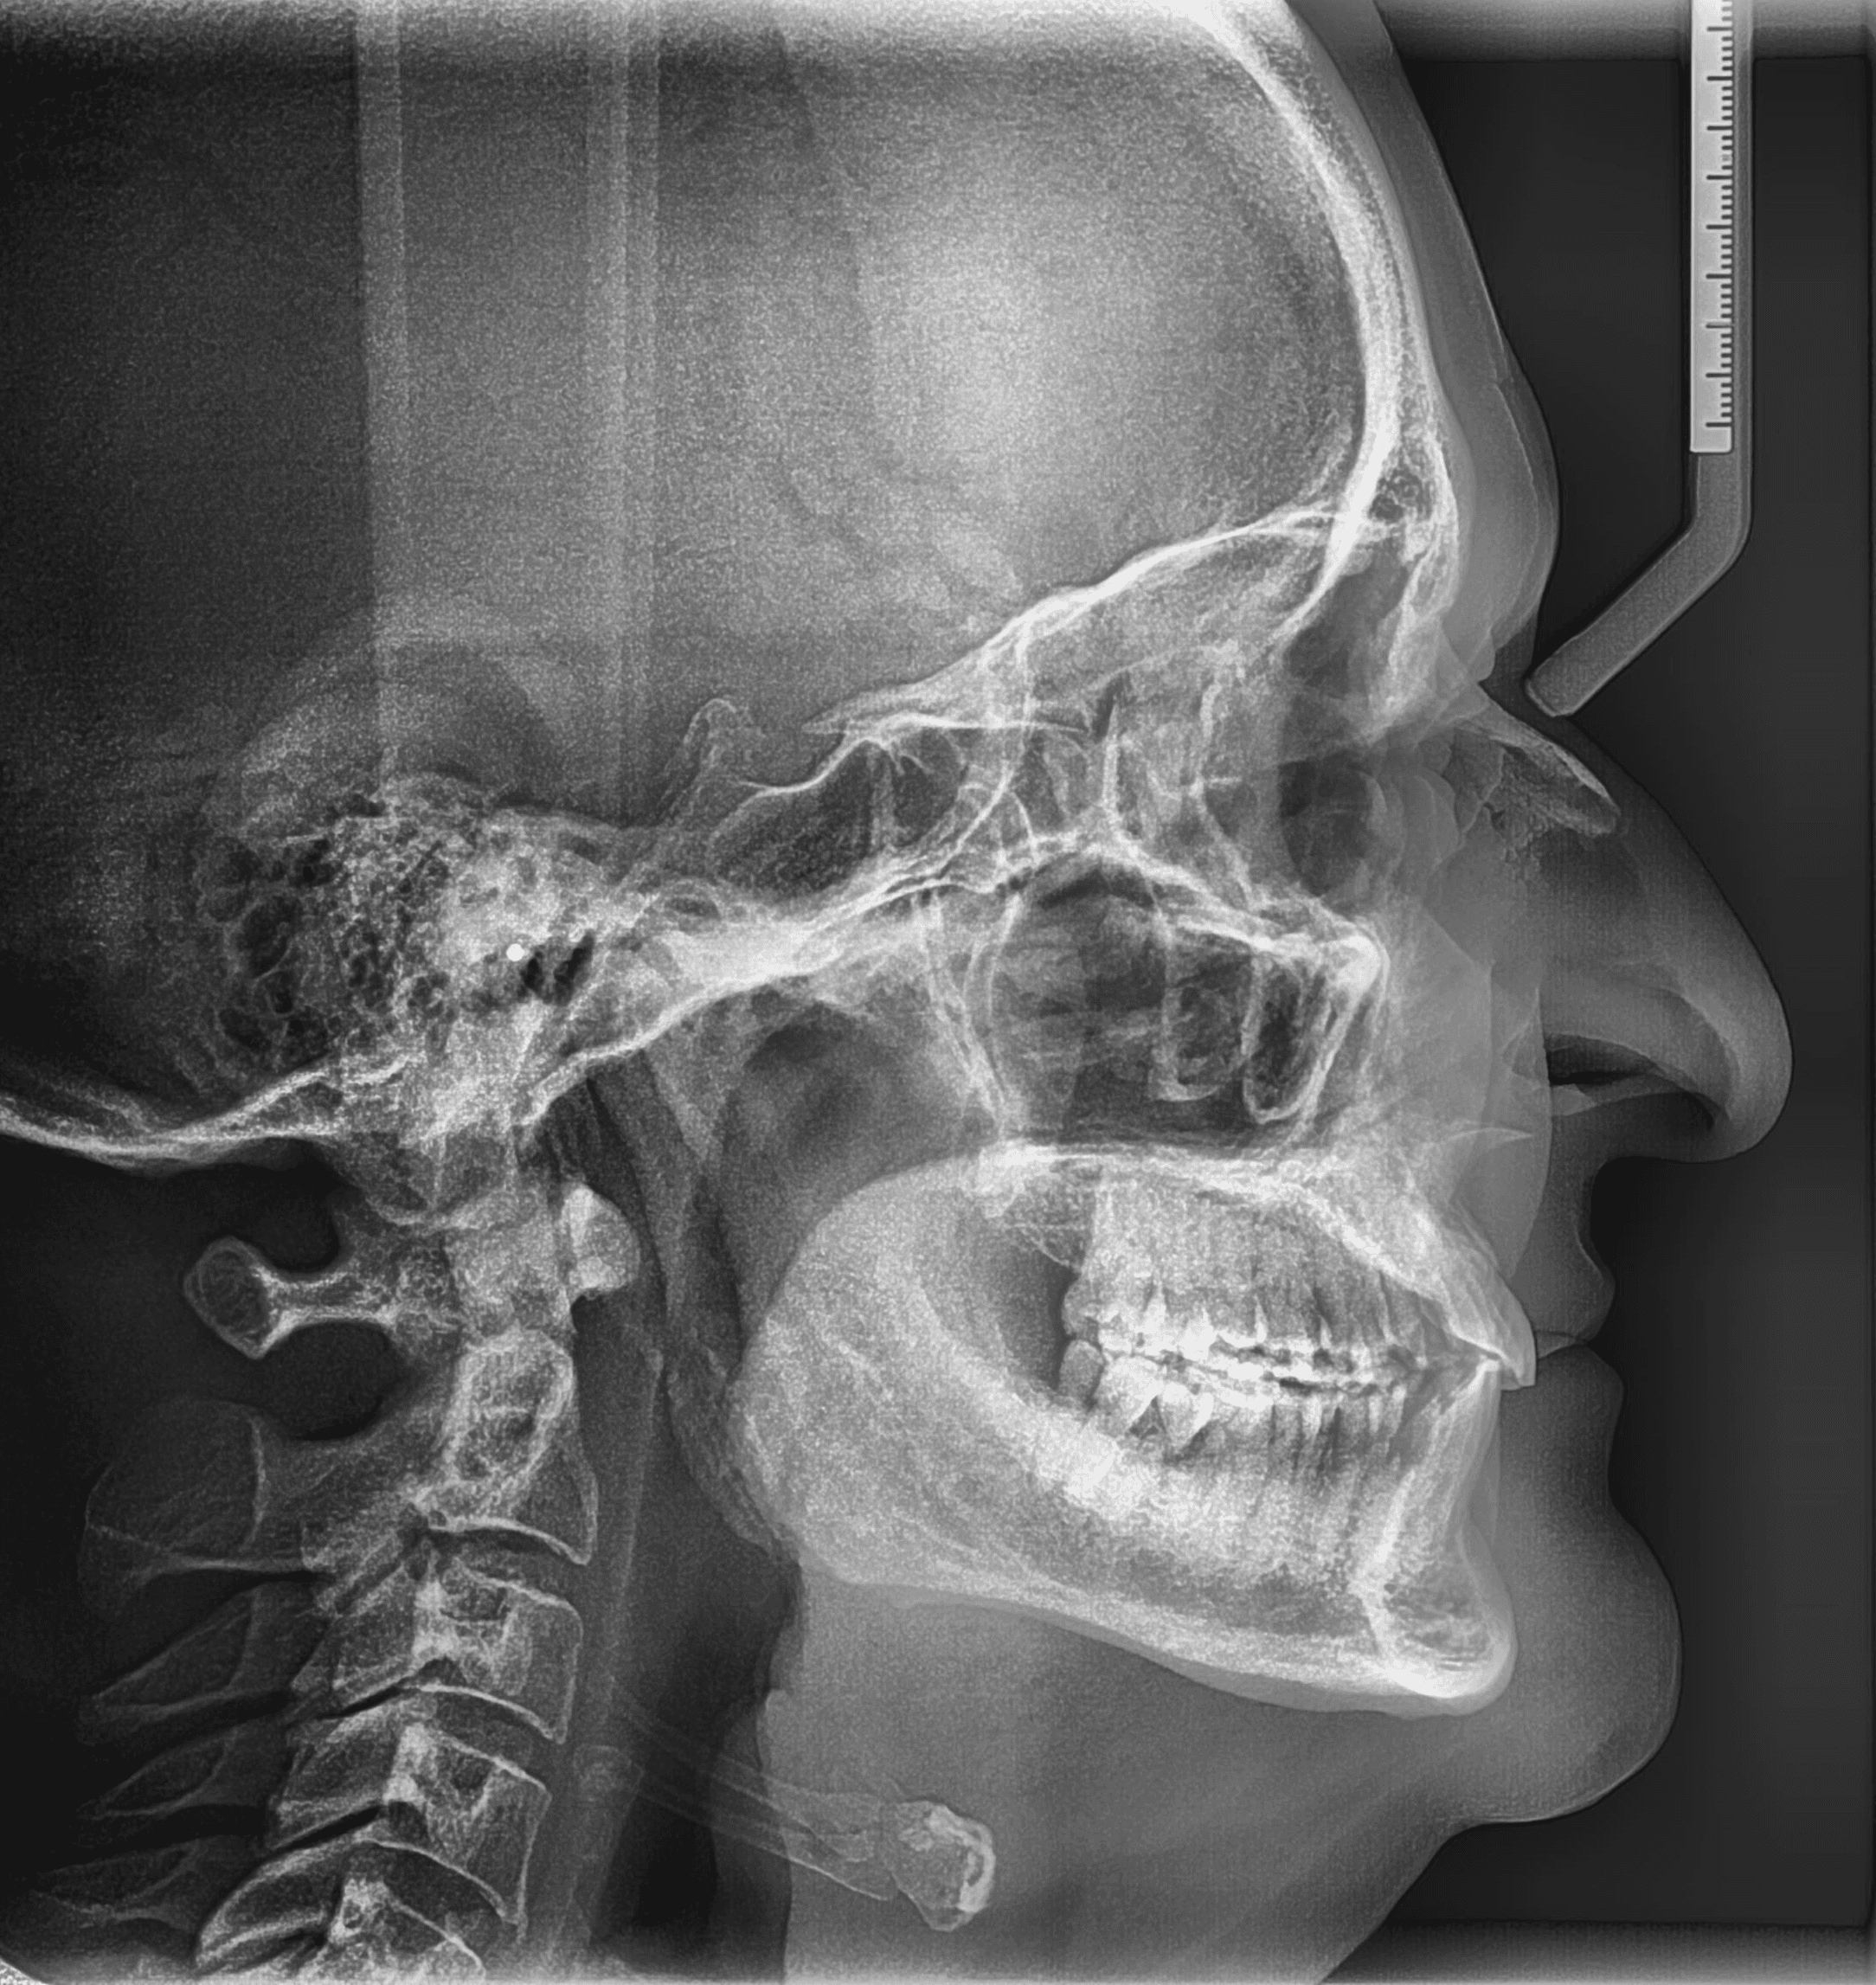

X-RAYS